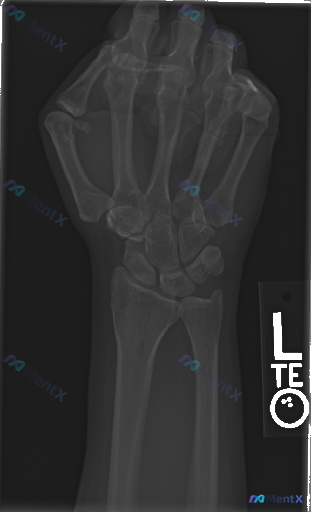

整理到一份左侧腕关节正位X光片的影像分析资料,想和大家讨论下这类情况的临床思路。 影像表现梳理: - 腕骨(舟骨、月骨、三角骨等)序列、形态大致正常,未见明确骨皮质中断或错位;桡骨远端、尺骨茎突、掌骨基底部也未见明确骨折线。 - Gilula三条弧线走行光滑连续,舟月间隙、月三角间隙未见明显增宽;桡...